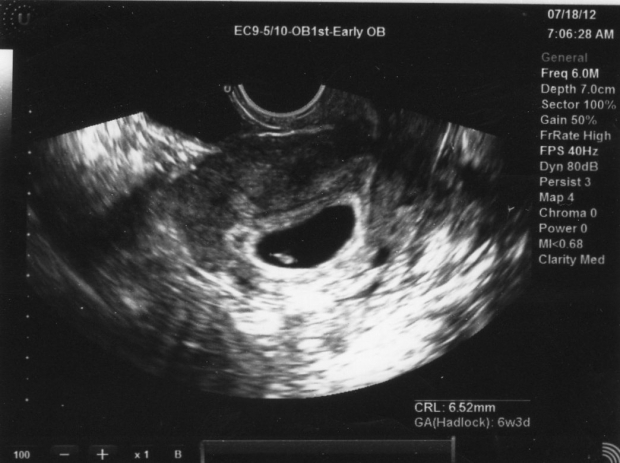

УЗИ: 6-ая неделя беременности

На шестой неделе беременности ультразвуковое исследование позволит увидеть эмбрион, который уже значительно увеличился и теперь сопоставим по размеру с горошиной. Специалист будет измерять его длину от темени до копчика, что поможет точно определить срок беременности и наиболее вероятную дату родов. Размер матки также немного увеличивается. На этом этапе можно подтвердить наличие беременности даже с помощью наружного УЗИ, то есть через живот.